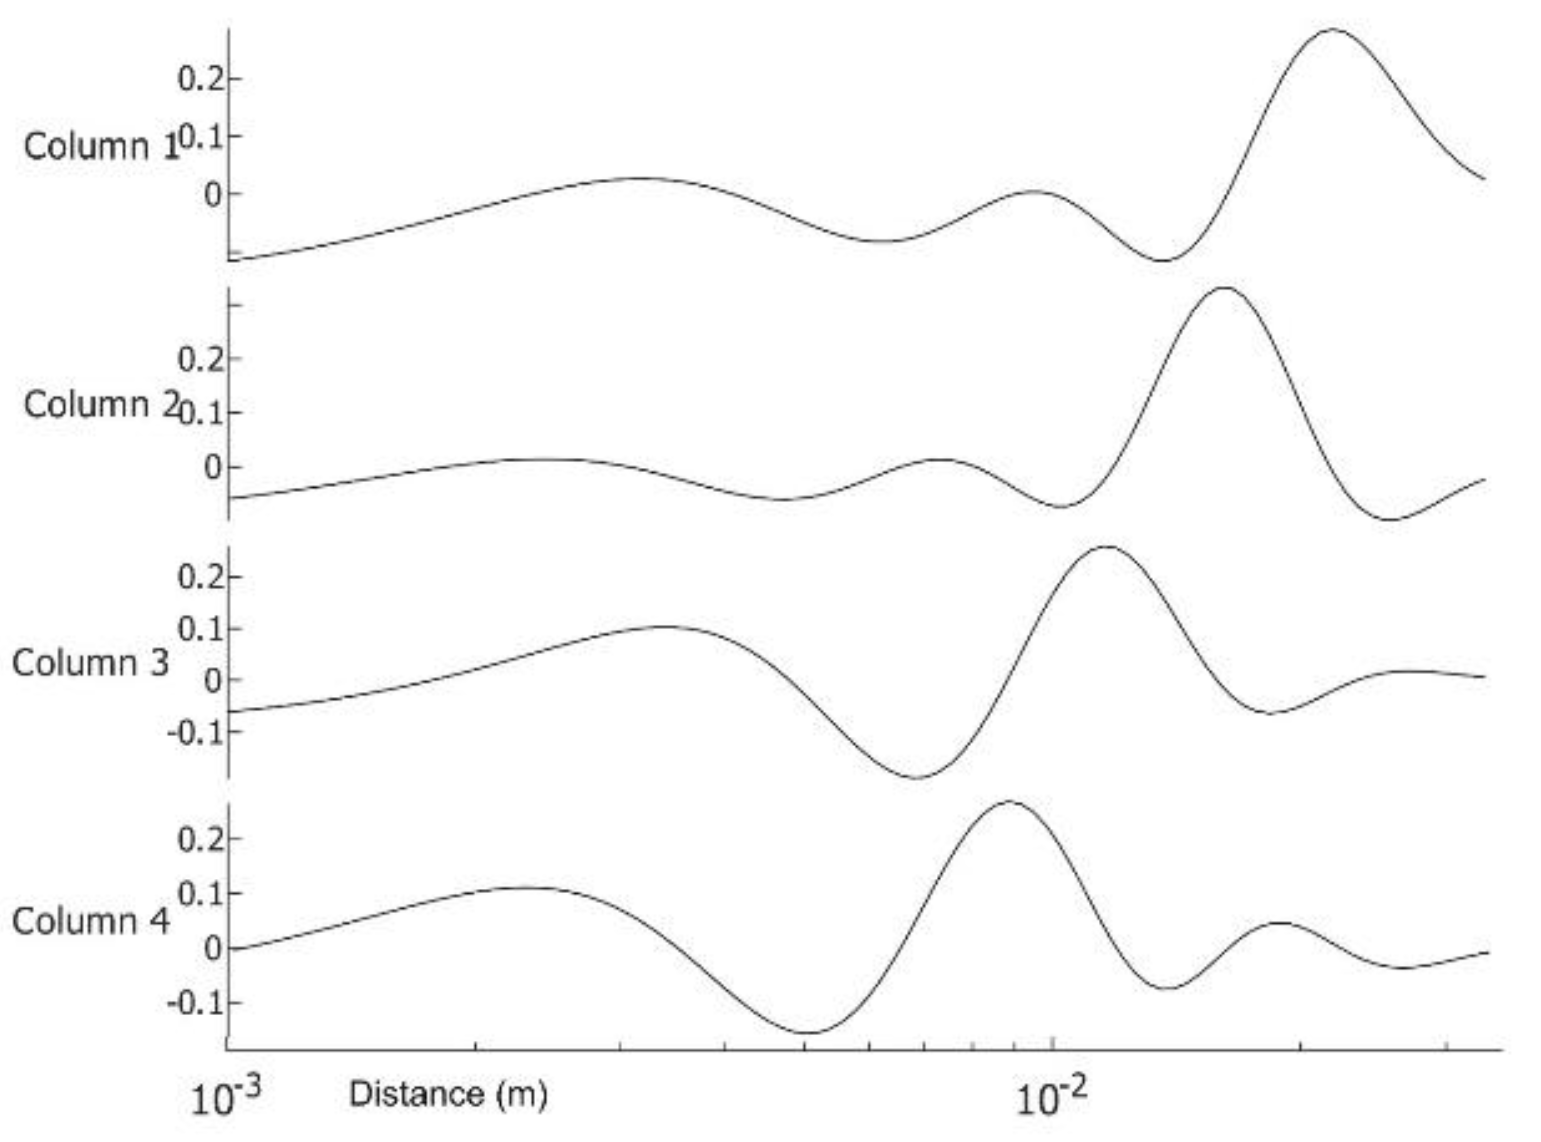

3.3. Analysis

Appendix B. Matrix Factorization

Appendix C. Excitation Extraction